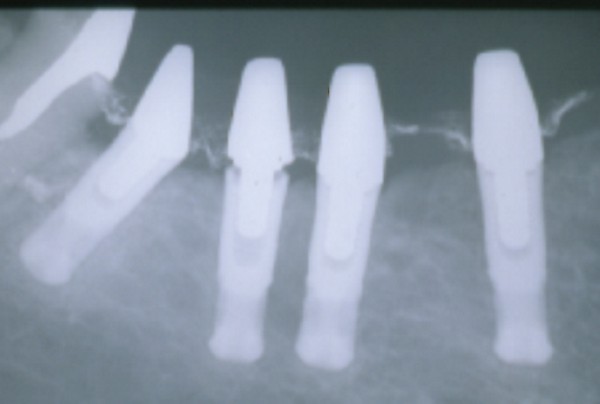

Radiográficamente se observa una barra sumamente extensa sobre cuatro implantes, la que ejerce un brazo de palanca excesivo (Fig.24).

Erosiones desmedidas a nivel de las piezas posteriores (fig.25), pérdida de un implante distal y el corte necesario del brazo distal de la barra (Fig.26).